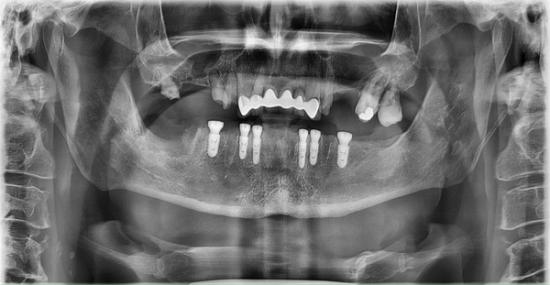

After Photo